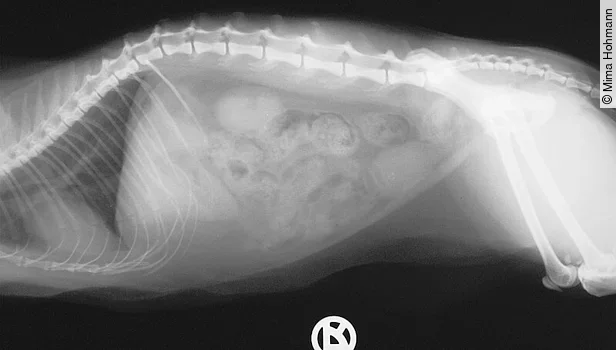

Bei der Palpation des Abdomens fallen bei der chronischen Obstipation die vermehrte Füllung der Darmschlingen und die harten Kotballen auf ([Abb. 5]).

Besteht die Obstipation längere Zeit, versucht die Katze durch Belecken des Abdomens wieder Bewegung in den Darm zu bekommen und die bestehenden Schmerzen zu „entfernen“, was ihr aber leider nicht gelingt. Fragen an den Besitzer, wie der Kot der Katze aussieht, wie die Konsistenz des Kotes beschaffen ist und wie oft die Katze Kot absetzt, helfen bei der Behandlung. Aus meiner Erfahrung kann ich sagen, dass oft ein „Leber-Feuer“ vorliegt.

Wie man sieht, sollte man eine Katze, die sich die Haare am Abdomen ableckt, auf alle Fälle röntgen. Der Vorteil des Röntgens: Man sieht nicht nur die Veränderungen an den Gelenken und der Wirbelsäule, sondern auch die Obstipation, Kristalle, Blasen-, Nieren- und Gallensteine, sondern auch Neoplasien, die ebenfalls ausstrahlende Schmerzen verursachen können.